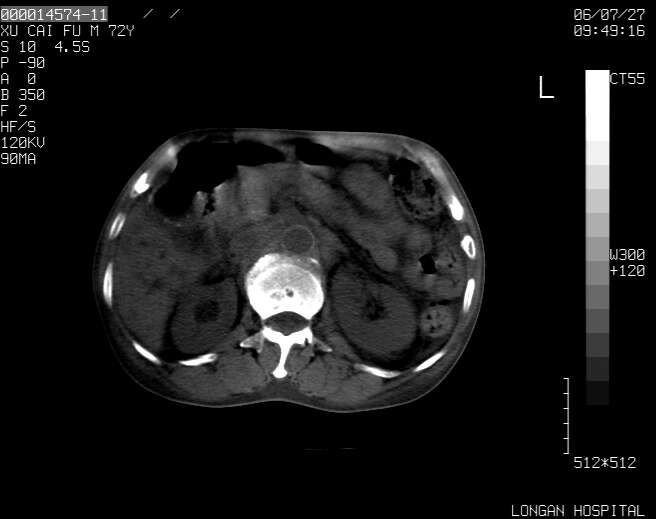

以下是引用winter在2006-7-30 20:14:00的发言:[br]1、考虑胆囊癌伴胆道侵犯并高位胆道梗阻、肝内多发转移、腹膜后淋巴结转移。[br]2、右肾轻度积水。[br]3、老人家72岁了胰腺头体尾部均较饱满,不过未见密度异常及其他异常征象。[br]4、腹水。

以下是引用jiajie在2006-7-31 7:10:00的发言:[br]考虑肝转移瘤,腹膜后淋巴结增大。[br]胃癌不能除外,建议胃镜检查。